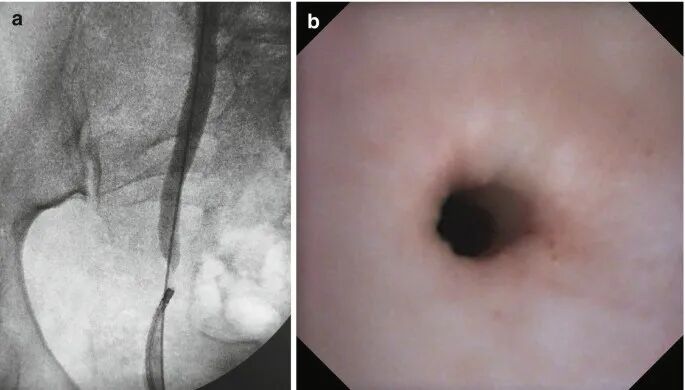

逆行肾盂造影显示输尿管粘膜呈手风琴样束,但未出现全层损伤,表现为缺乏造影剂外渗、全长输尿管通路保留以及上近端输尿管充盈。这些发现可诊断输尿管套叠,本病例是取石篮尝试取出一个相对较大的输尿管结石。

逆行肾盂造影 (a) 显示右输尿管远端狭窄。(b) 输尿管镜视图显示缺血性粘膜,伴同心狭窄